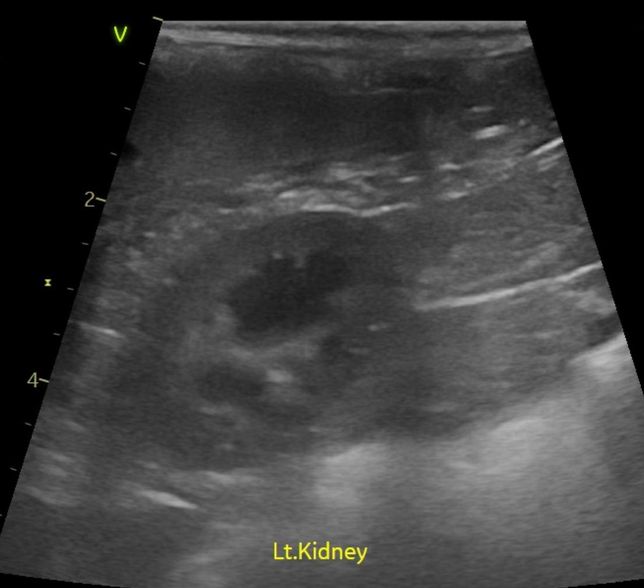

- 반려동물 건강반려동물Q. 강아지 신장결석 칼슘옥살 스트루바이트 둘중 어느것 같아보이는지요?강아지 신장결석 칼슘옥살 스트루바이트 둘중 어느것 같아보이는지요? 그냥 보시기에 만약에 판별이 가능하다면 알려주심 정말 감사하겠습니다. 병원만 3곳 다녔고 소변검사에 방광천자 제외하고 전부다 해봤는데 현재 6개월이 넘어갔는데 무슨 결석인지도 모르는 상태고 결석 크기는 신장 양쪽에 점점 커지고 있는 상황이라 이대로는 가만 있을수가 없어서 이렇게나마 질문글 올립니다.. 부디 알려주심 정말 한생명 살리는샘치고 정말 감사하겟습니다.